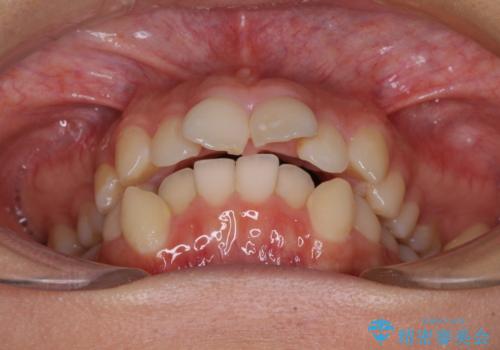

- 咬み合わせと、前歯のデコボコや八重歯、飛び出した口元を気にして来院された患者様です。

上顎は歯列不正が強く、右側臼歯部の咬み合わせは歯1本分ずれている状態でした。

補助装置を用いて奥歯の咬み合わせを改善しながら歯列を後方に移動させ、上下左右第一小臼歯を4本抜歯することで八重歯や口元の突出感を改善することとしました。